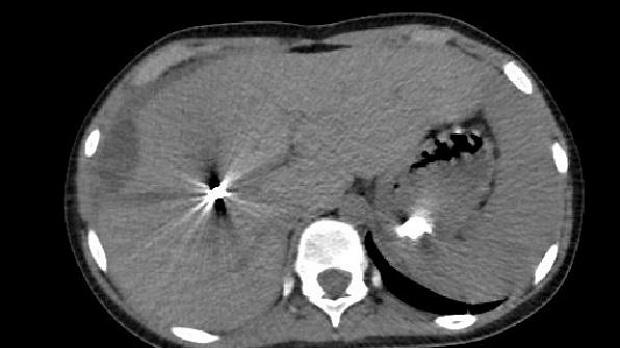

Пациент К. 13 лет с тяжелой травмой печени. В фундальном отделе по задней стенке определяется четко ограниченный участок гиперемированной, отечной, неровной слизистой оболочки с белесоватым налетом. Локализация процесса объясняется тем, что пациент длительное время находился на лечении в отделении ОРИТ (в горизонтальном положении), получал эрадикационную терапию (в том числе Де-Нол) в рамках комплексного лечения. При КТ ОБП в паренхиме правой доли печени - две металлические клипсы (результат эмболизации). А в просвете желудка определяется включение металлической плотности. У врачей возникло подозрение на проглоченное инородное тело, однако это было исключено предшествующей ЭГДС, на которой, кроме локального участка инфильтрации, инородных тел выявлено не было.